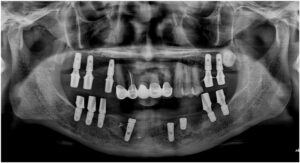

파노라마 촬영을 통해

임플란트가 정확한 위치와 방향으로

식립 된 것을 확인하였습니다.

모든 치료가 마무리된

파노라마 사진과

구강 내 사진인데요.